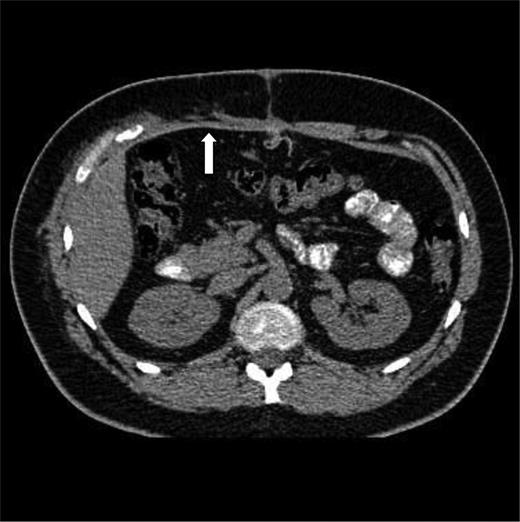

Trauma series computed tomography (CT) scans demonstrated a flail segment between the sixth and eight ribs with disruption of the intercostal muscles and a small right haemothorax (Fig. 1a). In the abdomen, there was hepatic contusion with an intrinsic liver injury (Fig. 1b). Blood was noted around the liver with minor active haemorrhage. The right abdominal wall was ruptured—the right rectus abdominis muscle had been torn from its costal attachments to the midpoint. The hepatic flexure of the colon had herniated through the intercostal muscles of the eighth and ninth ribs and was lying adjacent to the fractured ribs (Fig. 1c). Both small and large bowel had herniated through the abdominal wall lateral to rectus abdominis, but remained covered by external oblique (Fig. 1d). Herniation of small and large bowel immediately adjacent to the fractured ribs raised the suspicion of occult bowel injury not detected on CT.

(a–d) Initial CT imaging performed as part of the secondary survey.

CT at 10 weeks after the injury and primary repair. The mesh is seen in the anterior abdominal wall (arrow).